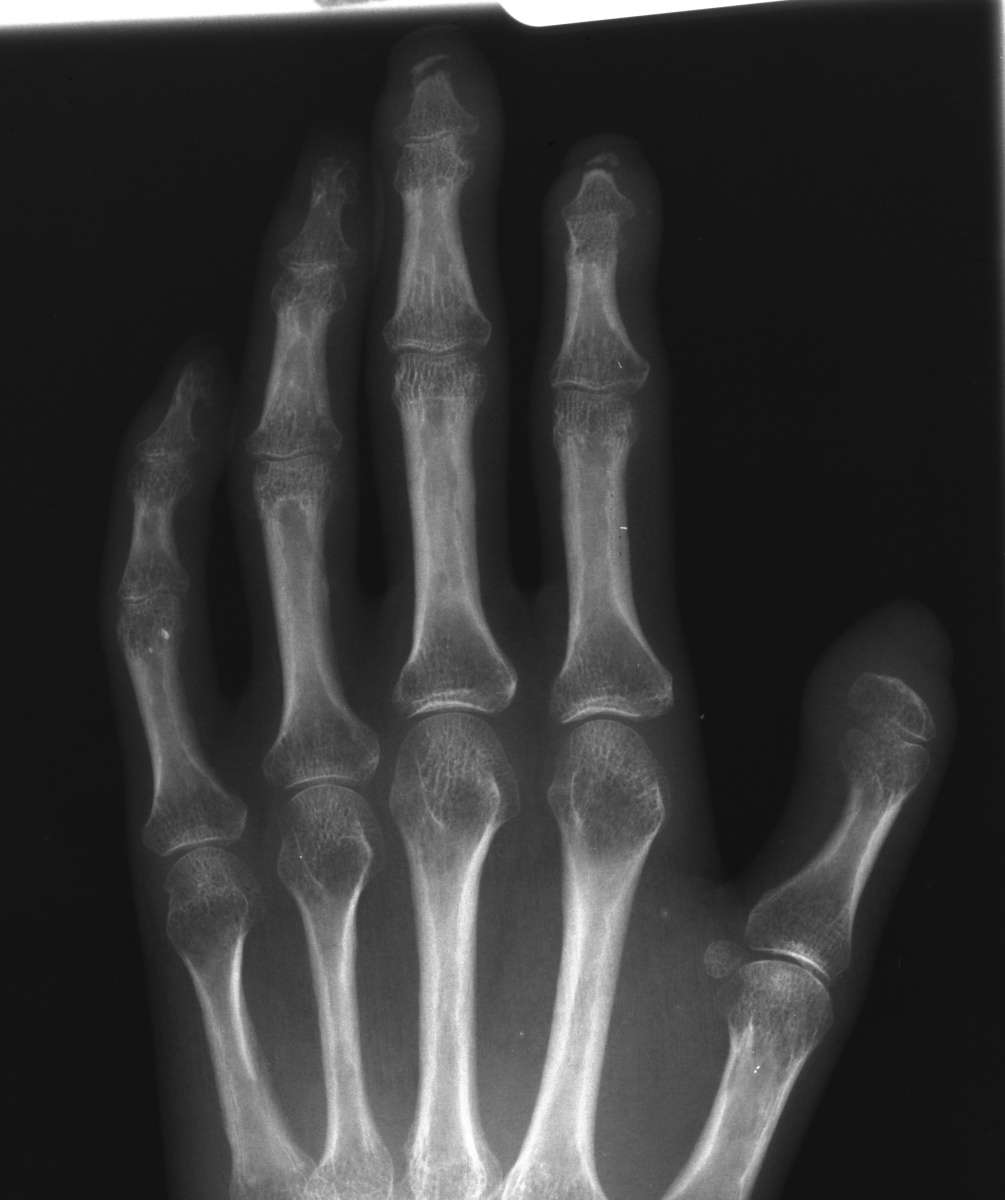

Clinical Example: Scleroderma, Calcinosis and Acroosteolysis

Scleroderma is a polymorphic condition , variably associated with a variety of conditions including joint stiffness, subcutaneous calcification and acroosteolysis. This patient with scleroderma demonstrates all of these conditions. This is most commonly associated with the finding of anticentromere antibodies.